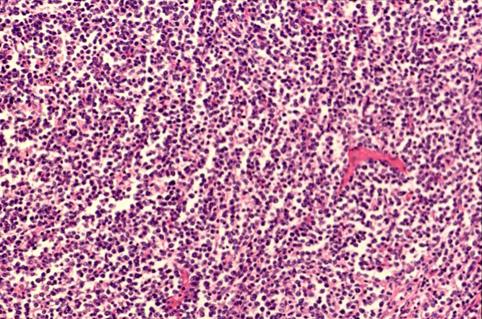

Linfoma Maligno de Multiples tumoraciones en el duodeno

Tumor Maligno del Sistema Linfático/Linfoma Maligno

parte(separada por órganos)

duodeno/descendente

Micro

35 - 40

presente(simultáneo)